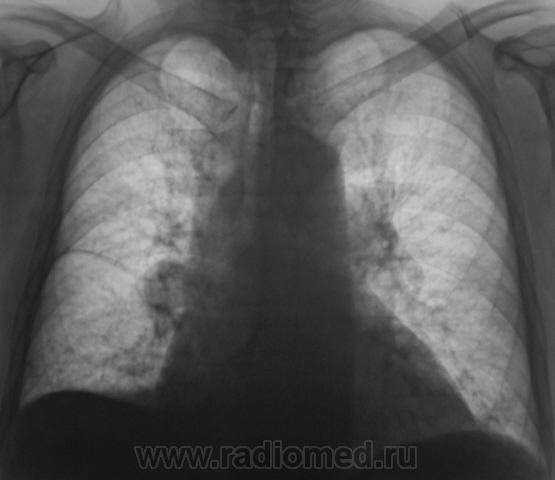

Произведены томограммы.

Продолжение.

Здравствуйте Almo! Томограммы выполнены в стандартных срезах - 7, 9, 11 см.

Вот раздумываю послать на КТ или не посылать. Пациент ничего и слышать не хочет о поездке в областной центр.

А что там в легких: фиброз, склероз, диссеминация? Почему этого не видно на томо?

На "томо" шикарно видно:

1. Гиповентиляцию правого лёгкого.

Выйдет что-то  типа пустого выстрела. Дядьке -100 лет, курец с 3-4 лет. И т.д.